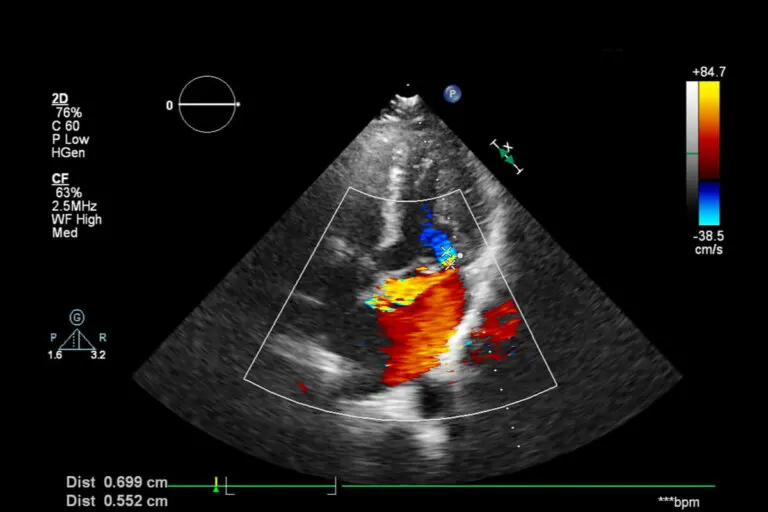

En la forma Doppler de la ecografía se visualiza el flujo sanguíneo en tonos rojos y azules.2. Dúplex

En esta ecografía a color, una computadora otorga tonos a las ondas sonoras y cada uno de ellos expone en tiempo real la dirección y la velocidad de la sangre.